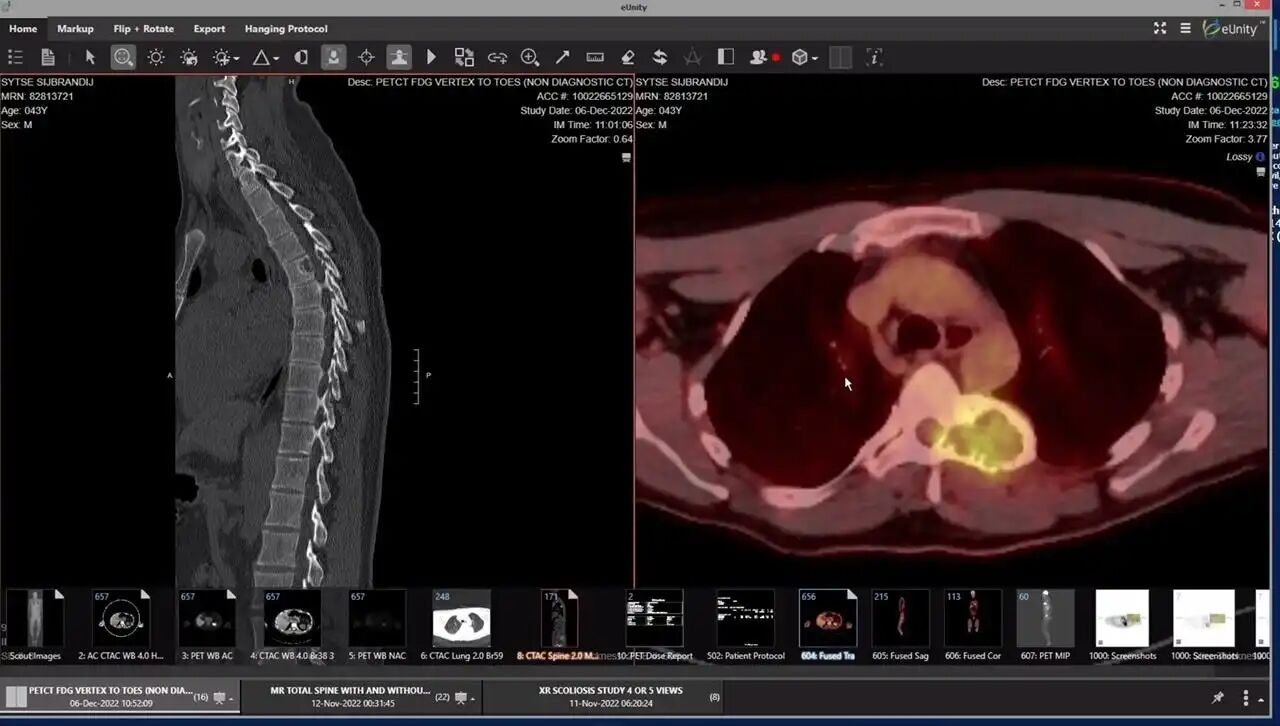

中间的是sib

做了X光检查后,发现他的T5椎骨(胸椎第五节,位于上背部脊柱)上长出了一个约6厘米大的肿块。

2022年11月18日,他被正式确诊为成人骨肉瘤(osteosarcoma,一种恶性骨癌,多见于儿童和青少年,在健康成年人身上非常罕见,而且预后往往较差)。

于是,Sid在2023年他接受了椎骨切除手术、脊柱钛框架融合,以及多轮高强度放疗和化疗,过程非常艰难,曾4次输血维持生命,头发掉光,几乎无法下床。